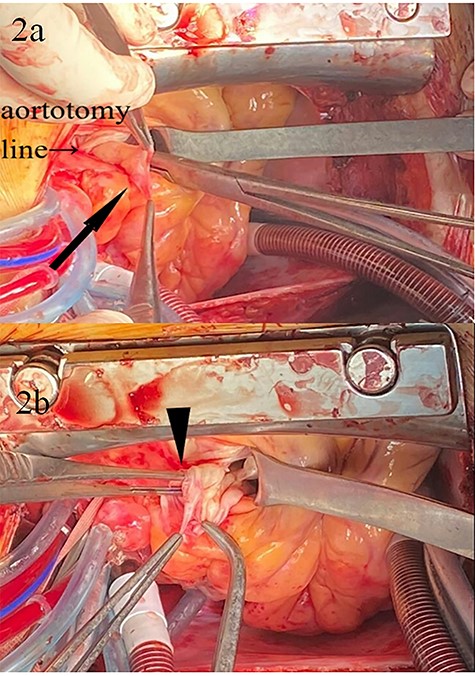

After sternotomy, cardiopulmonary bypass (CPB) was established with ascending aortic and bicaval cannulations, and systemic cooling lowered the body temperature to 32°C. The aorta was cross clamped, and an oblique aortotomy was performed. Antegrade cardioplegia was delivered into the coronary ostia with left ventricle venting via the right superior pulmonary vein. After arresting the heart, the ruptured SVA was identified by a thorough inspection (Fig. 2). There was no vegetation. The main pulmonary artery was opened with a vertical incision, and the VSD was found just below the aortic annulus.

Intraoperative images; (a) SVA (arrow); (b) the rupture site (arrowhead) of SVA; forceps are inserted into the ruptured hole.